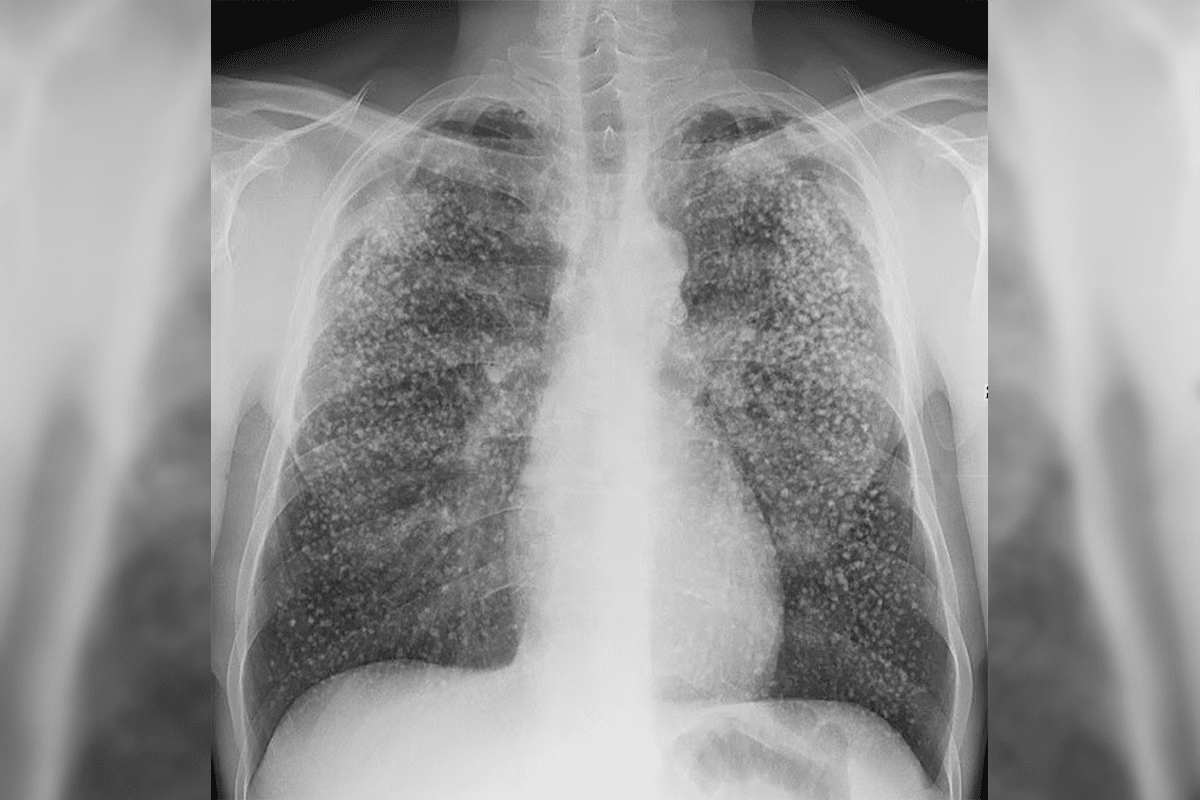

Recognizing PNA on Chest X-Ray: Key Radiographic Findings

Chest X-rays are key in diagnosing pneumonia. They help doctors make important decisions. There are specific signs on chest X-rays that help diagnose pneumonia accurately.

Alveolar Infiltrates and Consolidations

Alveolar infiltrates and consolidations are key signs of pneumonia, often from bacteria. These show up as darker areas on the X-ray. They mean there’s inflammation in the alveoli.

Interstitial Patterns and Opacities

Interstitial patterns and opacities are more common in viral or atypical bacterial infections. They look like net-like or patchy dark areas on the X-ray. This shows the lung’s interstitial tissue is involved.

Air Bronchograms and Silhouette Sign

Air bronchograms and the silhouette sign help diagnose pneumonia. An air bronchogram shows bronchi against a dark background. The silhouette sign hides normal structures with consolidation.

Lobar Consolidation in Bacterial Pneumonia

Bacterial pneumonia often shows up as lobar consolidation on X-rays. This is common in infections from Streptococcus pneumoniae. Lobar consolidation looks like a solid area in one or more lung lobes, with clear edges. Air bronchograms inside the consolidation show that the lung is filled with cells and fluid.

“The presence of lobar consolidation is a key diagnostic feature of bacterial pneumonia,” say radiologists. This helps doctors tell bacterial pneumonia apart from other lung infections.